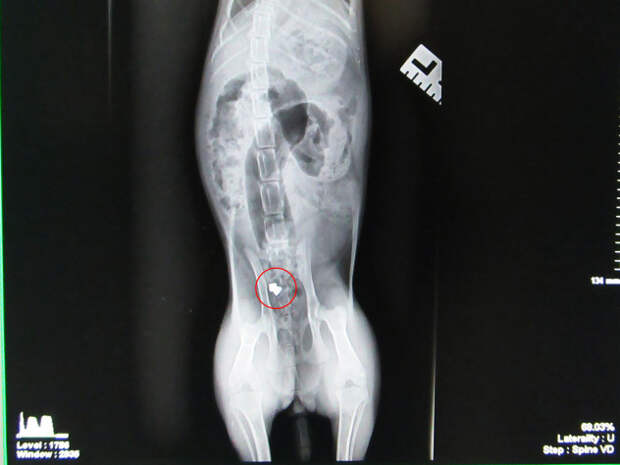

Исследования показали, что пуля все еще находится в задней части туловища кота. Крупное везение – немного дальше, и Санта либо погиб бы, либо остался парализованным, так как пуля могла разорвать позвоночник!